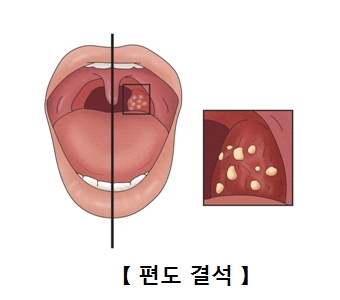

안녕하세요^ 무사하고 건강에 행복한 삶을 영위하고 싶은 생활건강 인플루언서 땡큐입니다.^^ 편도선에 생기는 악취를 가진 좁은 정도의 크기부터 손톱 정도의 크기까지 다양합니다.입 냄새를 유발하는 원인으로 구개편도선 표면에 존재하는 편도선이라는 부위에서 분비된 침소체가 구강 내 이물질과 섞여 생깁니다. 편도결석은 칼슘의 인산염과 탄산염으로 구성되어 있어 침 분비나 혀의 움직임에 의해 삼키거나 기침에 의해 반사적으로 외부로 나오게 됩니다. 편도결석은 보통 나쁜 냄새를 가지고 있어 휘발성 황화합물을 비롯한 악취를 유발하는 원인물질이 되고 식욕까지 변하기도 합니다. 심한 경우 병원에서 편도 구멍을 봉합하는 수술을 받아야 합니다. 그럼 편도결석의 원인과 증상, 편도결석을 빼는 방법에 대해 자세히 살펴보겠습니다.

편도결석의 원인

편도선이 표면의 편도선이나 내부에 세균, 백혈구, 세균의 시체, 지방산, 음식물 잔류물 등이 쌓여 생깁니다. 자연적으로 배설되는 경우가 많은데 배설되는 편도선 표면의 출구나 소와 부분이 좁은 경우 편도선 내부 속에 굳어져 큰 몸이 될 수 있습니다.

편도결석증상

치주질환 등 치과질환이 없는 상태에서 입 냄새를 스스로 느낄 경우 편도결석일 수 있습니다.오랄크로마 등을 이용한 구취측정기로 휘발성 구취가스 분석도 진단에 도움이 되고 또한 지속적인 목 이물감을 호소하는 환자도 많습니다.